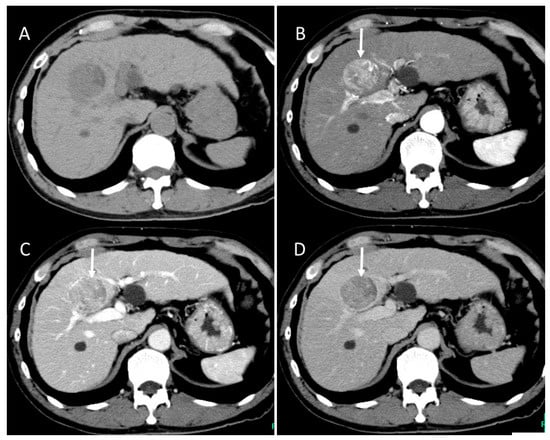

4.7. Combined Hepatocellular and Cholangiocarcinoma (cHCC-CCA)

4.8. Steatohepatitic HCC (SH-HCC)